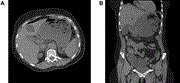

A rare case of retroperitoneal lymphangioma in a 74-year-old Chinese male

Hui Jun Lim and others

Journal of Surgical Case Reports, Volume 2021, Issue 2, February 2021, rjaa610, https://doi.org/10.1093/jscr/rjaa610